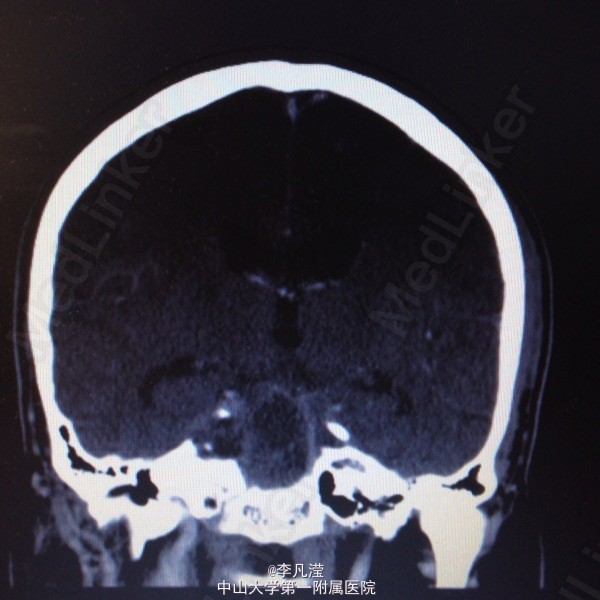

三叉神经鞘瘤一例

右侧中后颅窝底肿块,考虑三叉神经鞘瘤,右侧颞骨岩尖及海绵窦区骨质吸收,右侧麦氏孔扩大,侧脑室及第三脑室轻度积水。

右侧三叉神经鞘瘤